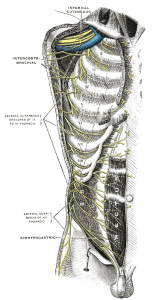

Auszug aus Wikipedia zu „Intercostal Nerv“:

Der Nervus intercostalis (dt. „Zwischenrippennerv“, auch Nervus subcostalis, „Unterrippennerv“) entspricht dem vorderen Ast (Ramus anterior) des jeweiligen Spinalnerven im Bereich der Brustwirbelsäule bzw. des Brustkorbes. Die Anzahl der Interkostalnerven einer Seite entspricht der Zahl der Rippenzwischenräume (Intercostalräume) – beim Menschen sind es also elf auf jeder Seite – bei zwölf Thorakalwirbeln/Rippenpaaren. (Der letzte, unterhalb der 12. Rippe laufende Nerv wird Nervus subcostalis genannt.) Sie versorgen motorisch die Zwischenrippen- und Bauchmuskulatur sowie die Haut im Bereich der Brust- und oberen Bauchwand. Sie verlaufen jeweils mit einer Arterie und einer Vene an der Unterkante der entsprechenden Rippe.

Der Nervus intercostalis (dt. „Zwischenrippennerv“, auch Nervus subcostalis, „Unterrippennerv“) entspricht dem vorderen Ast (Ramus anterior) des jeweiligen Spinalnerven im Bereich der Brustwirbelsäule bzw. des Brustkorbes. Die Anzahl der Interkostalnerven einer Seite entspricht der Zahl der Rippenzwischenräume (Intercostalräume) – beim Menschen sind es also elf auf jeder Seite – bei zwölf Thorakalwirbeln/Rippenpaaren. (Der letzte, unterhalb der 12. Rippe laufende Nerv wird Nervus subcostalis genannt.) Sie versorgen motorisch die Zwischenrippen- und Bauchmuskulatur sowie die Haut im Bereich der Brust- und oberen Bauchwand. Sie verlaufen jeweils mit einer Arterie und einer Vene an der Unterkante der entsprechenden Rippe.